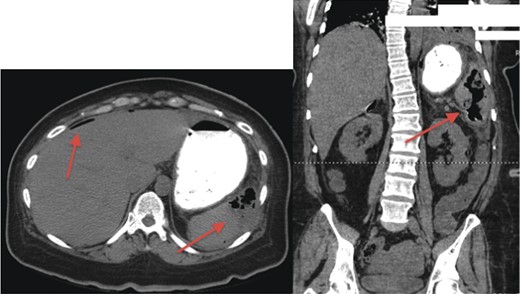

Her initial labs showed a normal WBC level of 8.3 thou/mcL; however, the patient was acidotic with a pH of 7.29 and a lactic acid level of 3.5 mmol/l. An acute abdominal series was obtained demonstrating free air below the right hemidiaphragm (Fig. 1). Physical examination showed a distended abdomen with tenderness, guarding and signs of peritonitis. The patient was subsequently boarded for an exploratory laparotomy with repair of perforated viscus, as that is the usual cause of pneumoperitoneum, especially under the right hemidiaphragm. Because the patient's vital signs stabilized after being resuscitated, the decision was made to obtain a CT scan to better assess the location of the perforated viscus. Much to our surprise, the patient did not have a perforated viscus, but a splenic abscess that had ruptured causing the pneumoperitoneum (Fig. 2).

CT scan demonstrating gas-forming splenic abscess and free air in the peritoneal cavity.